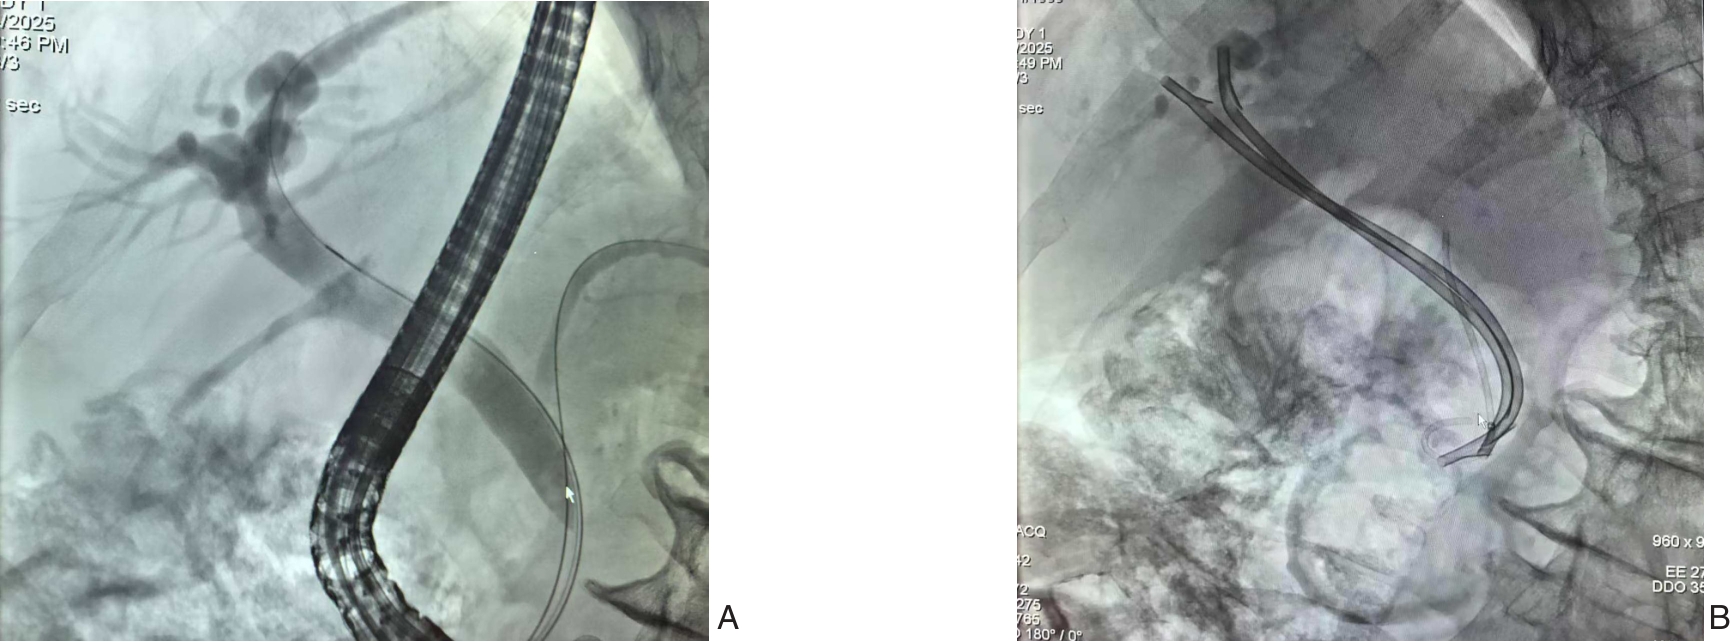

2025, 34(8):1783-1789. doi: 10.7659/j.issn.1005-6947.250076

摘要:背景与目的 肝内胆管癌(ICC)是一种起病隐匿、预后极差、初诊多为进展期的原发性肝癌,其治疗选择有限,预后差。本研究旨在探讨靶向治疗、免疫治疗与肝动脉灌注化疗(HAIC)联合应用于晚期ICC的转化治疗的潜力,为临床转化治疗提供参考。方法 回顾广东医科大学附属医院2021年11月收治的1例晚期ICC行靶向治疗、免疫治疗与HAIC联合治疗后成功转化并接受手术患者的诊治过程,并复习国内外相关文献。结果 患者为52岁男性,确诊为T2N1M0-Ⅲb期ICC。患者拒绝接受以吉西他滨联合顺铂为主的一线化疗方案,同意行靶向治疗联合免疫治疗与HAIC的综合治疗,在接受4个治疗周期后评估肿瘤达到部分缓解,具备实施根治性手术治疗的条件。患者随后接受了腹腔镜下肝S6段和部分S7段切除、胆囊切除以及肝门部和腹膜后淋巴结清扫术。术后患者规律行靶向免疫联合化疗的综合治疗方案。在疾病出现复发和转移后,化疗药物进行了相应调整。截至目前,患者无病生存期达15个月,总生存期超过3年。结论 靶向治疗、免疫治疗与HAIC三联方案可提高晚期ICC患者的转化机会并延长生存期,具有较好的安全性和临床应用前景,但其疗效仍需多中心研究进一步验证。